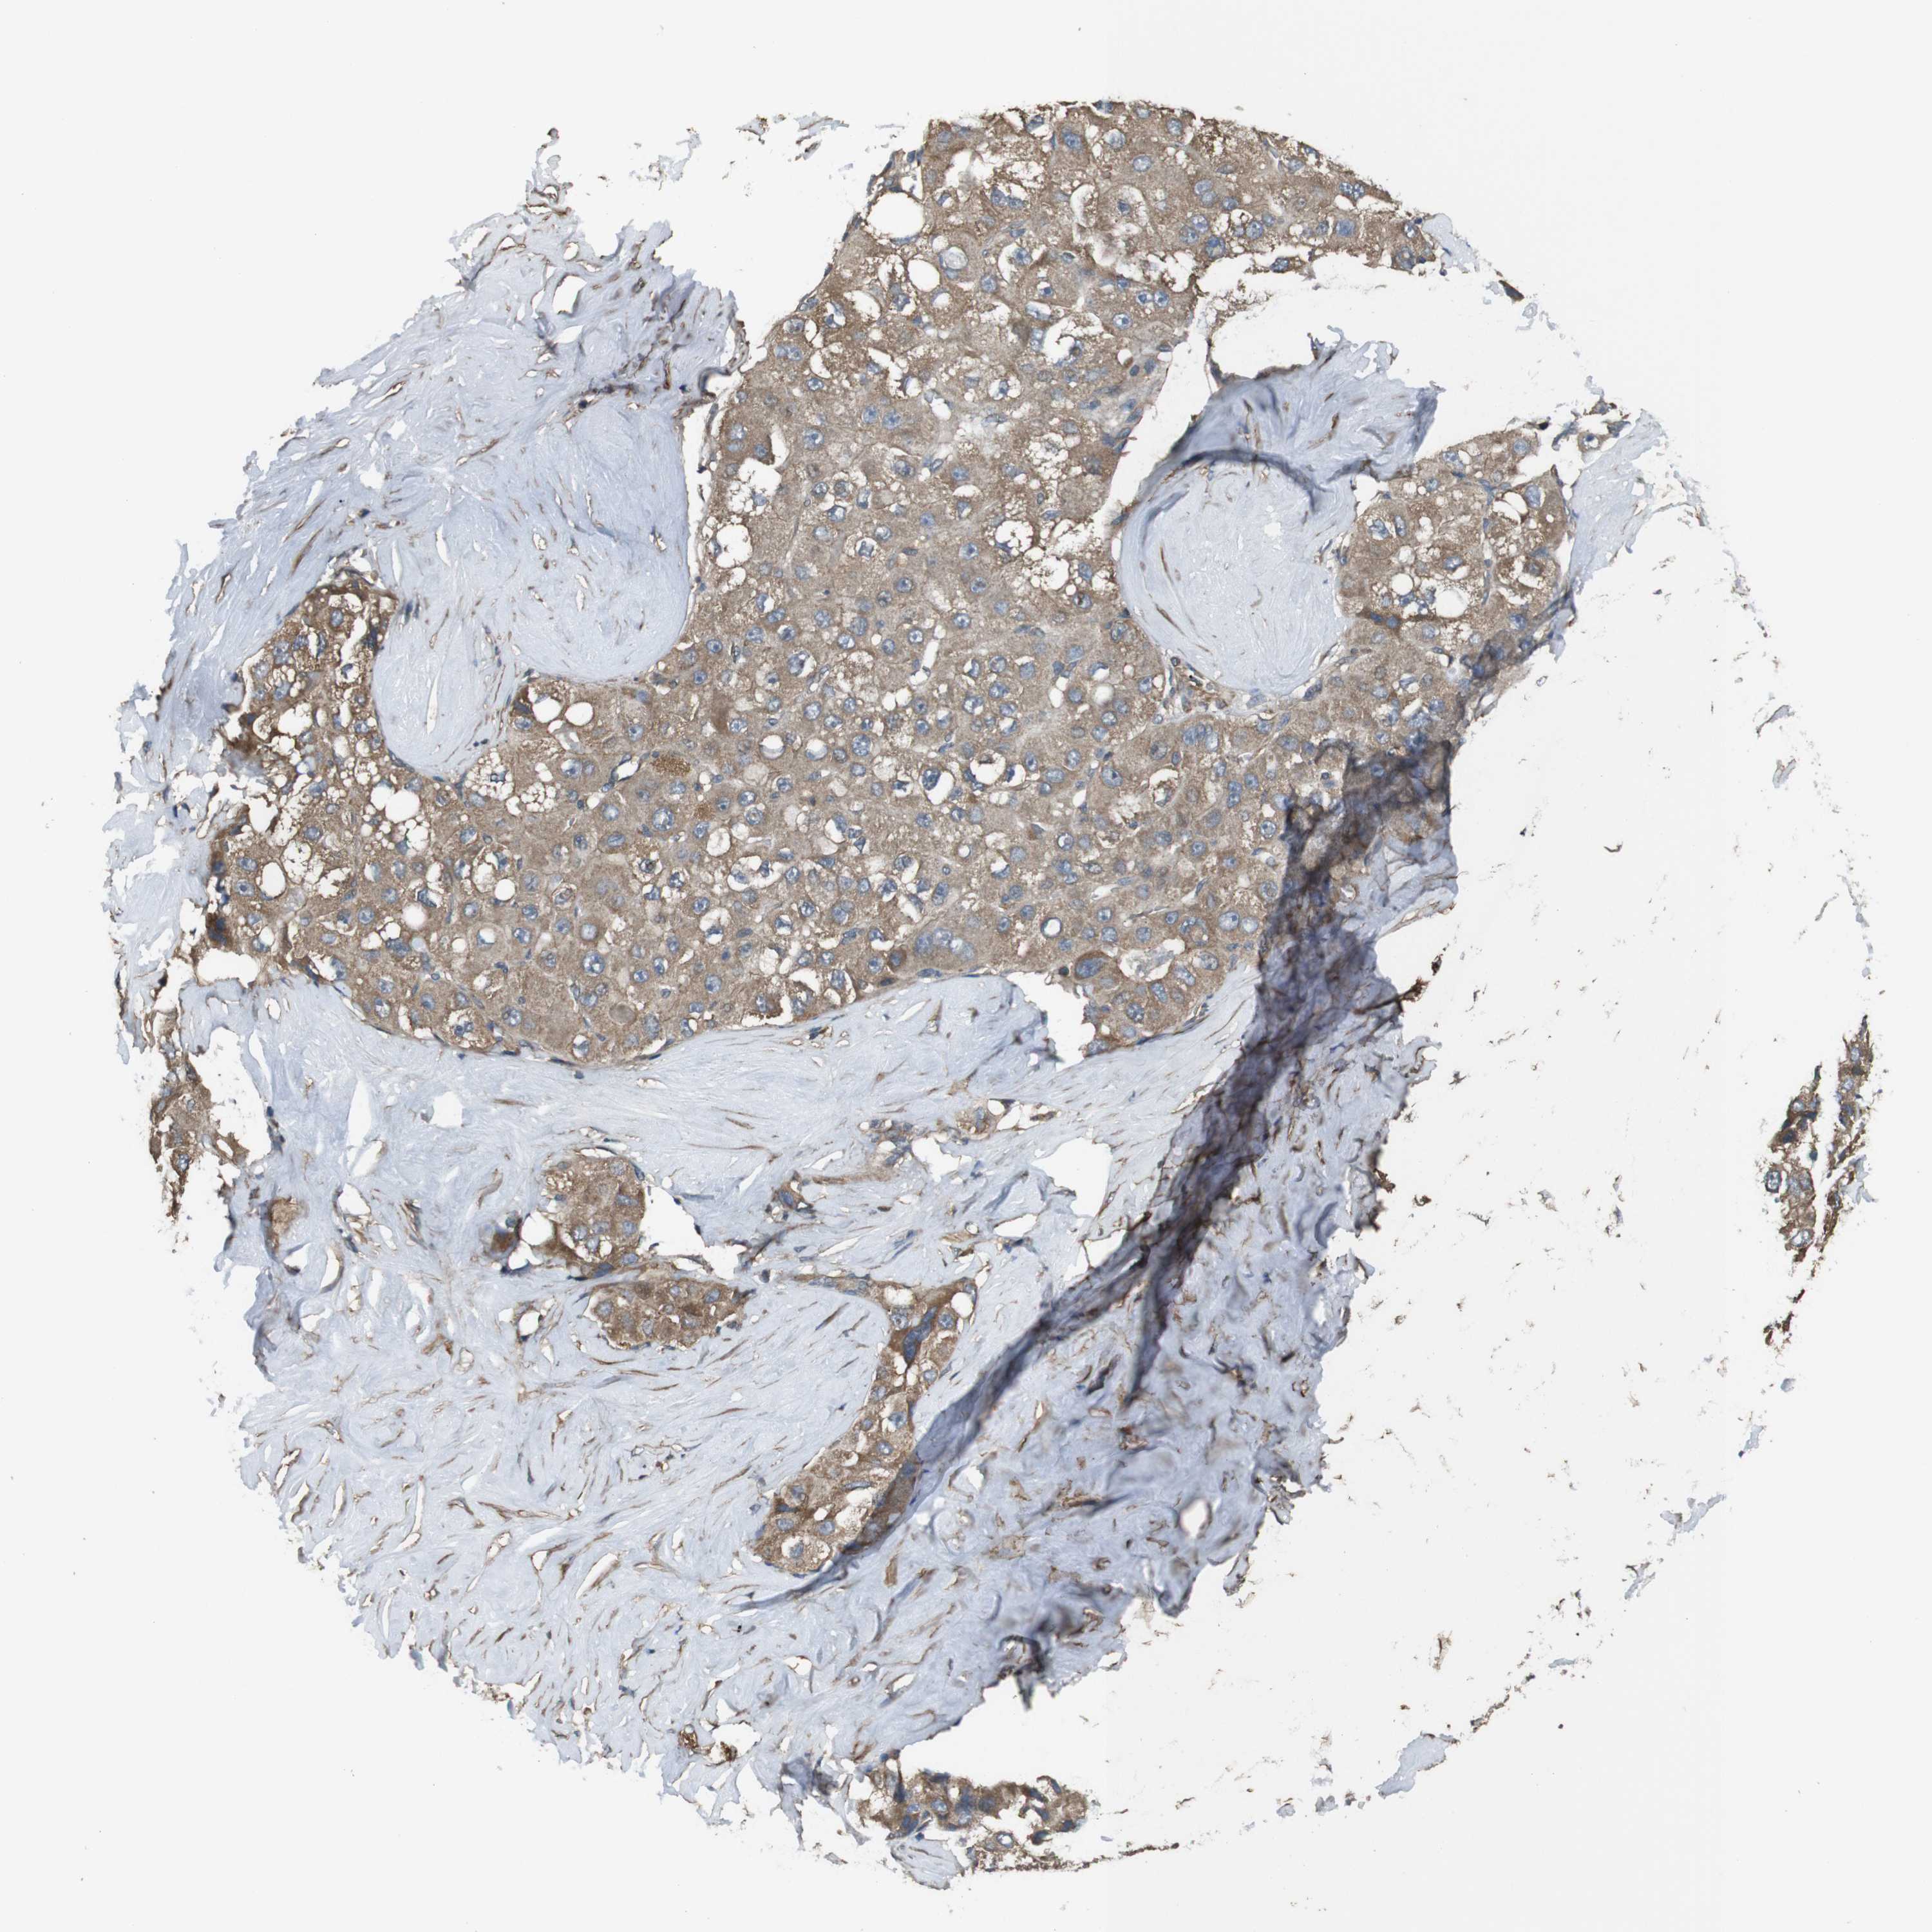

LIVER CANCER - Protein expressioni

A mouse-over function shows sample information and annotation data. Click on an image to view it in a full screen mode. Samples can be filtered based on level of antibody staining by selecting one or several of the following categories: high, medium, low and not detected. The assay and annotation is described here.

Note that samples used for immunohistochemistry by the Human Protein Atlas do not correspond to samples in the TCGA dataset.

Antibody stainingi

Antibody staining in the annotated cell types in the current human tissue is reported as not detected, low, medium, or high, based on conventional immunohistochemistry profiling in selected tissues. This score is based on the combination of the staining intensity and fraction of stained cells.

Each image is clickable and will lead to virtual microscopy that enables deeper exploration of all samples and also displays staining intensity scores, fraction scores and subcellular localization as well as patient and tissue information for each sample.

Antibody HPA014402

Staining

High

Medium

Low

Not detected

Intensity

Strong

Moderate

Weak

Negative

Quantity

>75%

75%-25%

<25%

None

Location

Nuclear

Cytoplasmic/membranous

Cytoplasmic/membranous,nuclear

Cholangiocarcinoma

Carcinoma, Hepatocellular, NOS